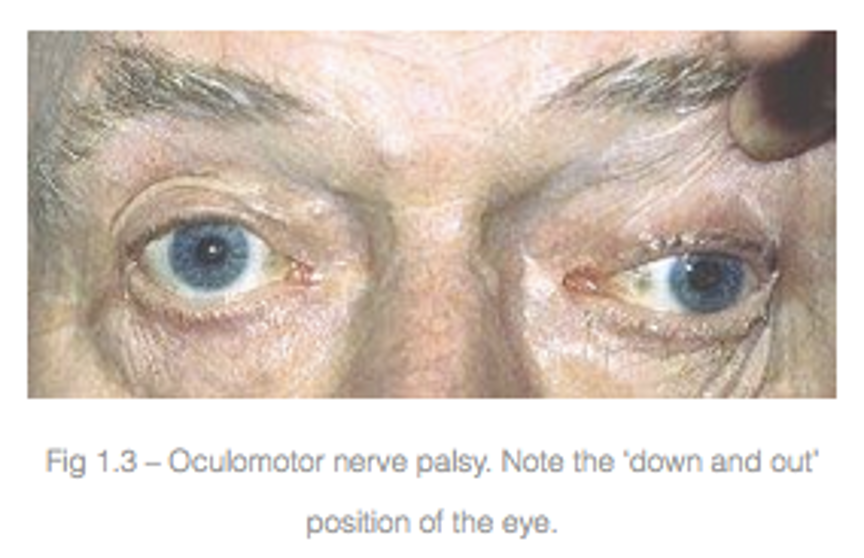

injure

injure

複視